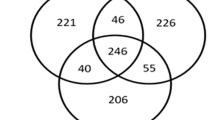

The fenestrated ciliary body capillary endothelia allow the flow of blood plasma across the ciliary stroma which helps in the secretion of aqueous humor by the ciliary epithelium. We were interested in proteins derived from ciliary body, which are directly relevant to its physiology, and not those derived from the blood diffusing into the ciliary body. There is a blood aqueous barrier, which permits solutes from the blood vessels of the ciliary stroma into the aqueous humor [11]. We compared the ciliary body proteome with human plasma proteome from Plasma Proteome Database [43] and aqueous humor proteome in order to get the ciliary body specific proteins. A total of 9,393 plasma proteins were compared with the ciliary body proteome and we observed that 896 proteins were unique to the ciliary body proteome as seen in Figure 4A. Proteins detected in the ciliary body were also compared to proteins previously reported in the aqueous humor [7, 44–47]. We found 211 proteins that were also reported in the aqueous humor proteome Figure 4B. Only seven of these 211 proteins were described in the plasma (Figure 4C). These unique proteins are CRYGD crystallin, gamma D (CRYGD), crystallin, gamma S (CRYGS) and crystallin, gamma C (CRYGC), which maintain the transparency and refractive index of the lens [48, 49]. Gamma crystallins have been involved in cataract formation due to aging or mutations. The source of these proteins is likely to be the aqueous humor and not the plasma, as the lens, where these are abundant is an avascular structure receiving all its nutrient supply from the aqueous humor. In addition the aqueous humor removes metabolic waste from the lens. Another molecule is pyruvate kinase muscle (PKM), which is involved in glycolysis and serves as a key regulator of energy metabolism in proliferating cells. Frizzled-related protein (FRZB) is secreted protein and plays a significant role in the loss of the Wnt signaling pathway in different type of cancers by down regulation of this gene [50]. Ubiquitin fusion degradation 1 (UFD1L) forms complex with nuclear protein localization 4 (NPLOC4) and valosin containing protein (VCP). NPLOC4 and VCP are also identified in this study. This complex is required for the degradation of ubiquitinated proteins [51]. Retinoschisin 1 (RS1) plays a significant role in the cellular organization of the retina [44, 45].

Comparison of the ciliary body proteome with the aqueous humor and plasma proteome. Panel A shows comparison of the ciliary body proteins with plasma proteins annotated in the Plasma Proteome Database. Panel B depicts comparison of the ciliary body proteome with aqueous humor proteome annotated from the published literature. Panel C shows a comparison of proteins that are common to the ciliary body and plasma with those that are common to the ciliary body and the aqueous humor.